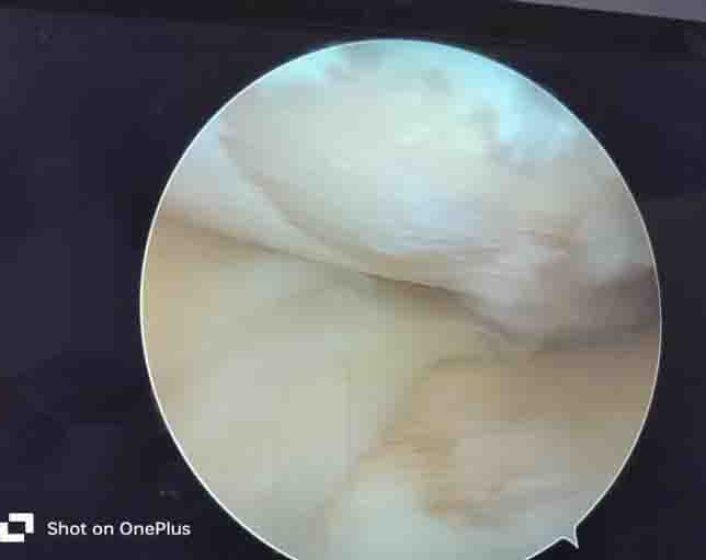

Cartilage Defect in Knee Pain